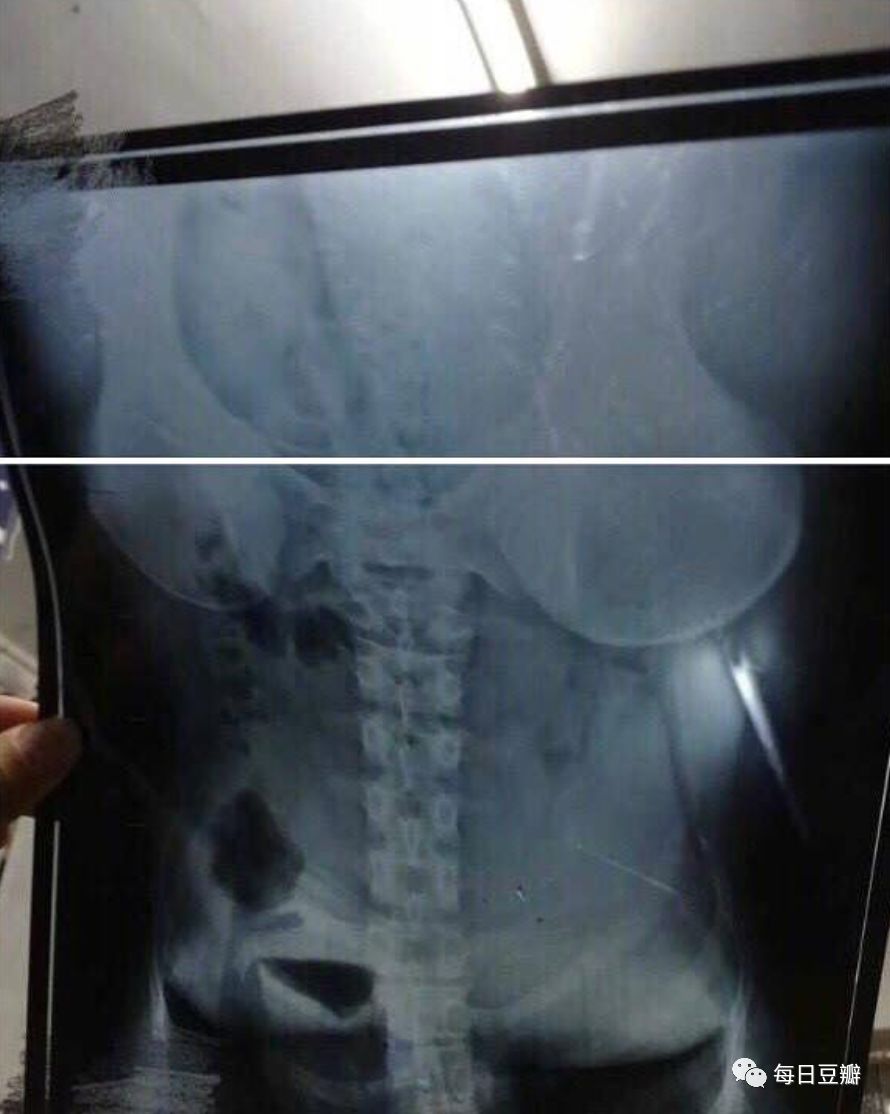

小八:· _ ·?不是这个角度,这是拍的肚子,你拿反了

你拿反了

拿反了

反了

了

正确姿势如下图